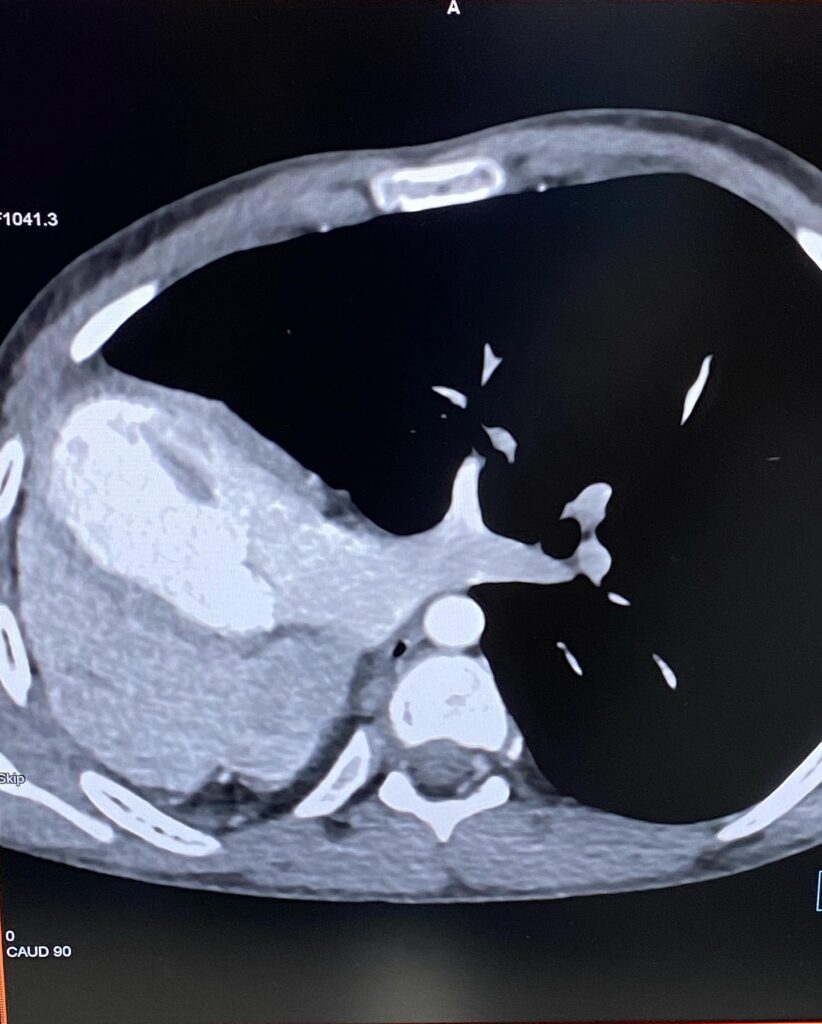

Մասնավորապես՝ 14-ամյա տղայի մոտ աջ թոքի թերզարգացածության պատճառով միջնորմը և սիրտը գտնվում են կրծքավանդակի աջ կեսում։

Արդյունքը տպավորիչ էր։ Երեխայի մոտ առկա էր աջ թոքի ագենեզիա (թոքը չի զարգացել, համապատասխանաբար բացակայում էին նաև աջ գլխավոր բրոնխը, աջ թոքային զարկերակը և աջ թոքային երակները), ինչի հետևանքով միջնորմը (այդ թվում սիրտը) տեղակայված է կրծքավանդակի աջ կեսում։

Սրտի նման տեղակայումը հեմոդինամիկ շեղումներ չի առաջացրել. երեխան ունի կառուցվածքային առողջ սիրտ։